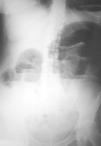

Mujer de 54 años, sin antecedentes de interés, que acude por presentar desde hace 2 días dolor en hemiabdomen superior tipo cólico acompañado de vómitos fecaloideos de 12 horas de evolución. Exploración física: afebril, destaca un abdomen doloroso, distendido y timpánico con aumento de los ruidos hidroaéreos, el resto sin hallazgos de interés. La analítica de sangre (hemograma, bioquímica básica y hemostasia) presenta una leucocitosis (12.900 leucocitos, 86,1% neutrófilos), el resto de los valores están dentro de la normalidad. Radiografía simple de abdomen (fig. 2): dilatación de las asas de intestino delgado y edema de pared. Radiografía en bipedestación (fig. 3): niveles hidroaéreos. Se realiza laparotomía exploradora ante el cuadro de obstrucción de intestino delgado, hallándose serositis segmentaria en yeyuno con restos larvarios de AS. Tras instaurar sueroterapia y dieta absoluta se produce una mejoría de su estado general en las siguientes 72 horas, con desaparición del dolor abdominal, reiniciándose la alimentación oral que tolera sin complicaciones. Ante el antecedente epidemiológico de ingesta de boquerones en vinagre 48 horas antes de la intervención, se realizaron tests cutáneos que fueron positivos para AS y negativos para la batería de pescados de consumo frecuente; así como niveles de IgE total (267 UI/ml; normal < 200) y específica para AS (44; normal < 0,35 RU/ml). La paciente fue diagnosticada de anisakiasis intestinal, se repiten las determinaciones de IgE cada 3 meses, normalizándose sus valores de IgE total despues de un año y permaneciendo elevada la IgE específica (15 RU/ml).

Figura 2. Radiografía simple de abdomen anteroposterior.